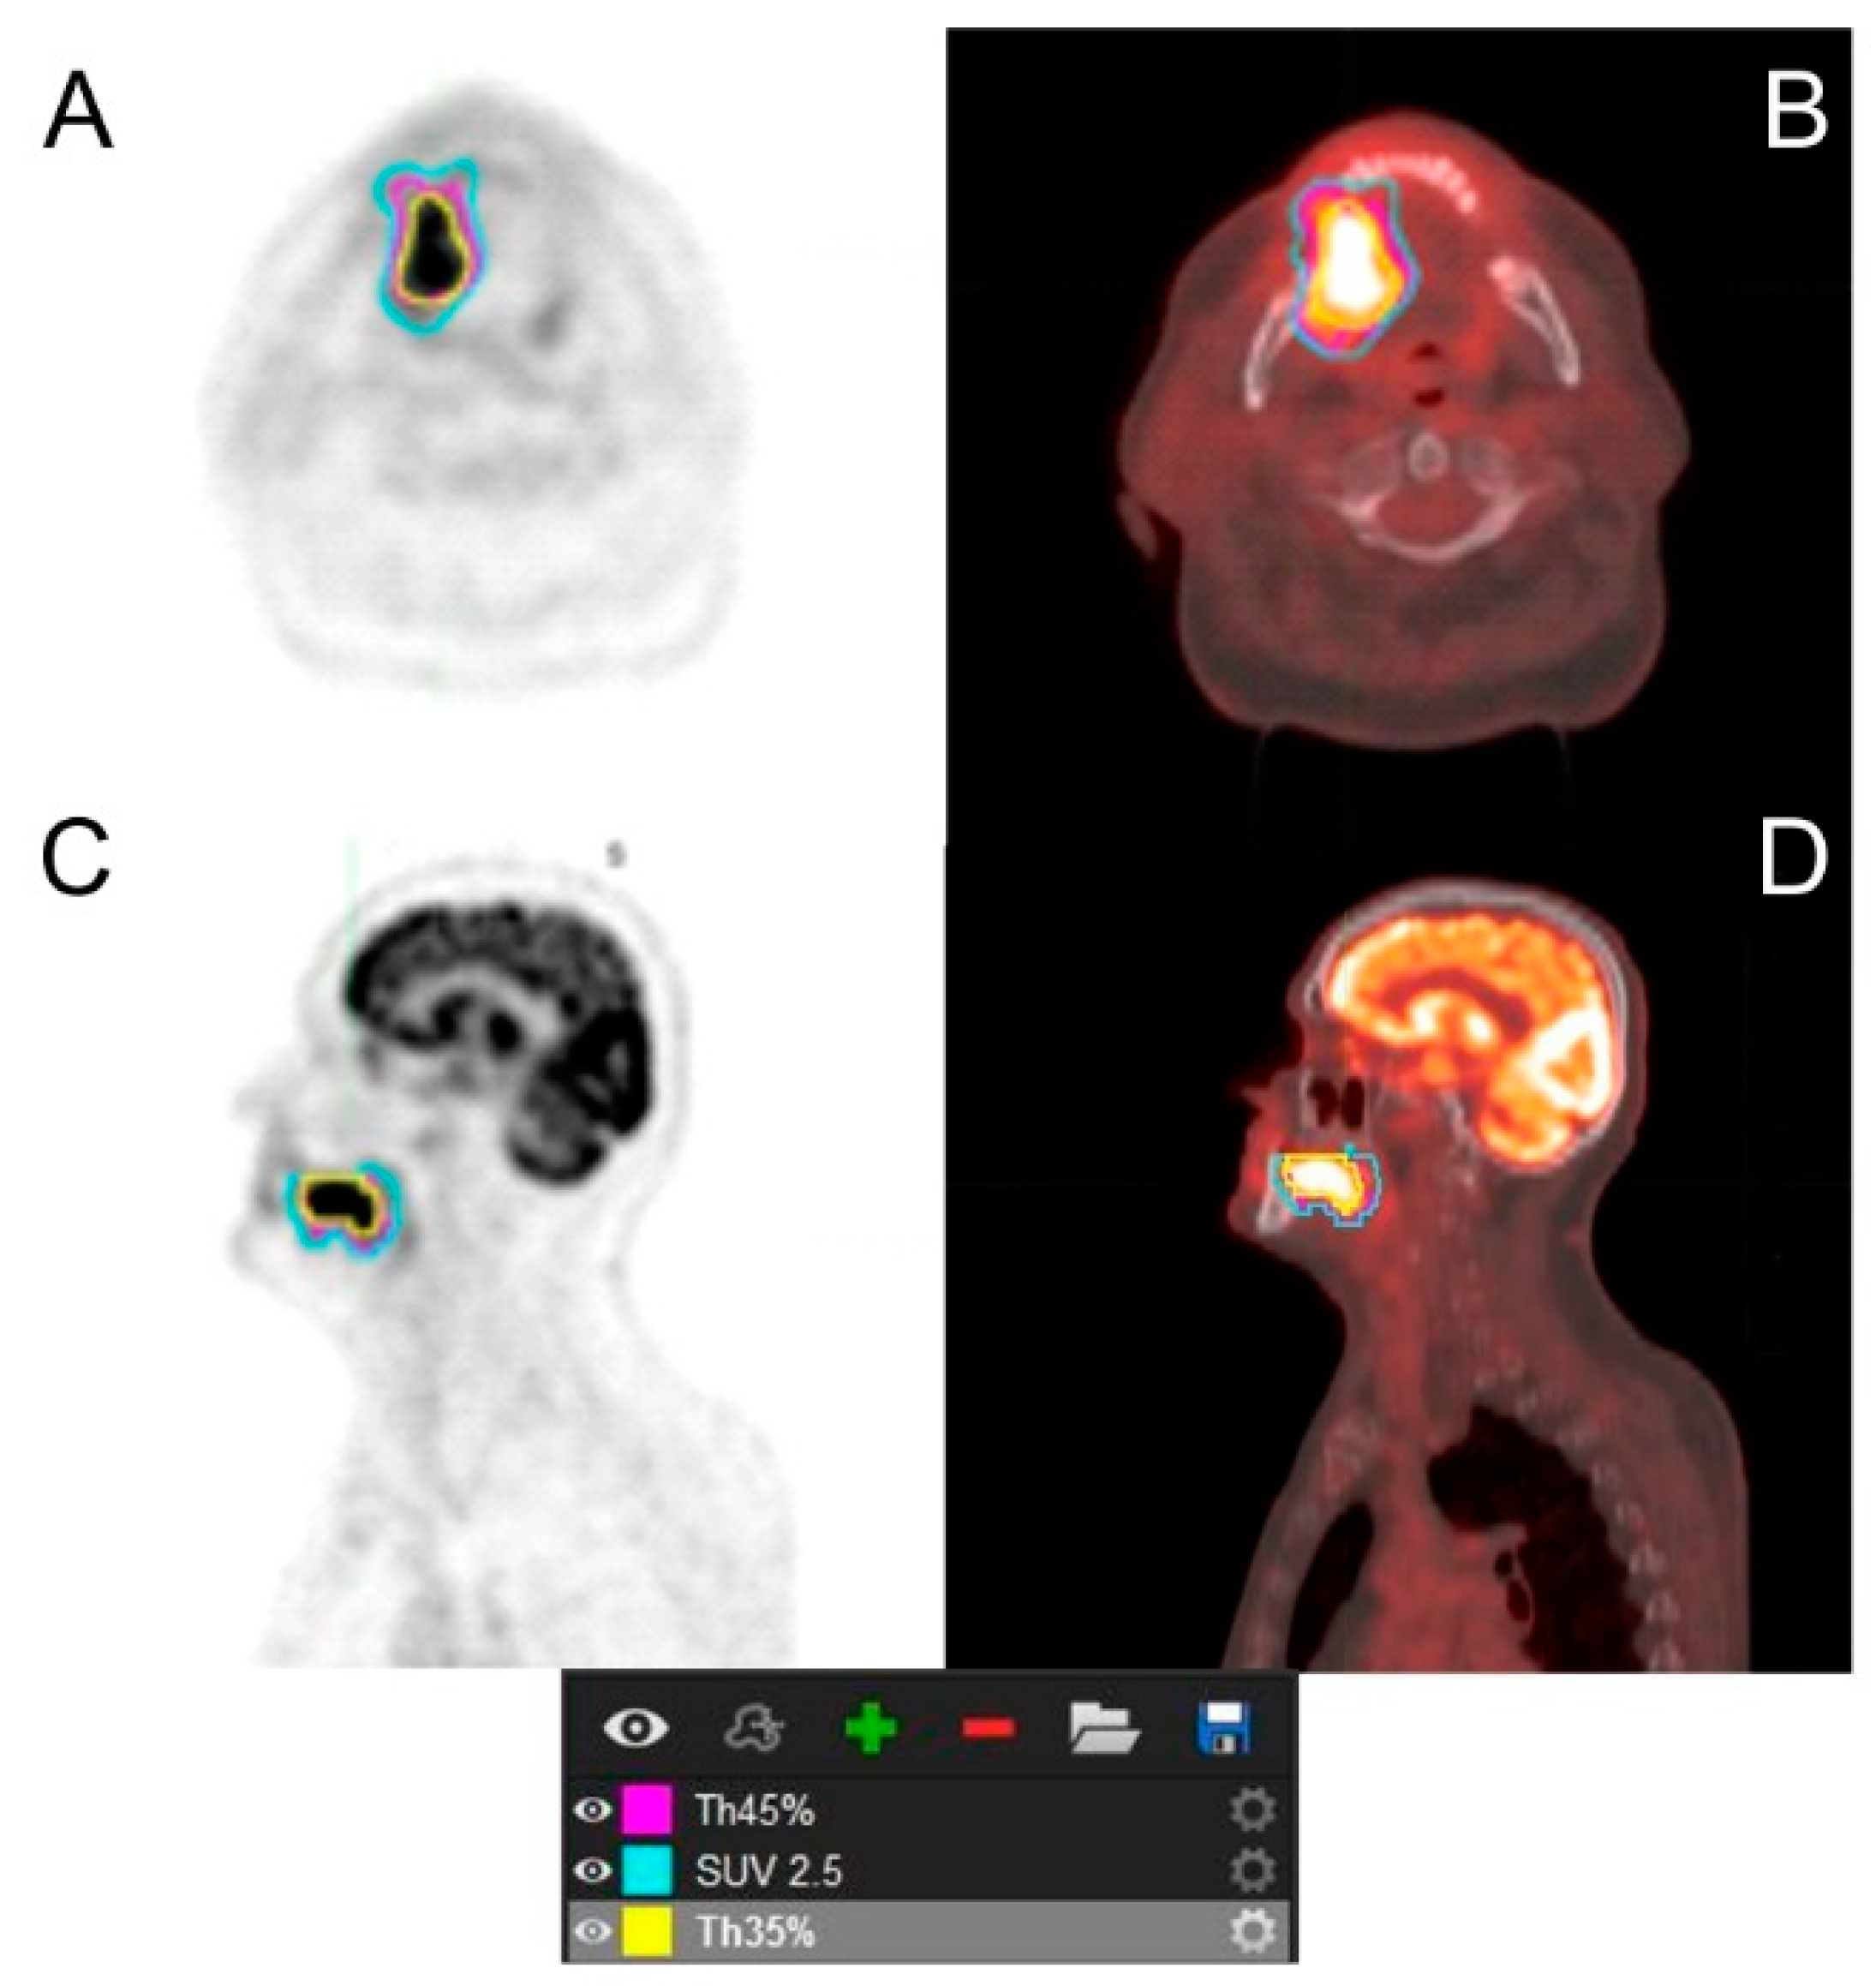

- Cegła, P.; Burchardt, E.; Wierzchosławska, E.; Roszak, A.; Cholewiński, W. The effect of different segmentation methods on primary tumour metabolic volume assessed in 18F-FDG-PET/CT in patients with cervical cancer, for radiotherapy planning. Contemp. Oncol. 2019, 23, 183–186. [Google Scholar] [CrossRef]